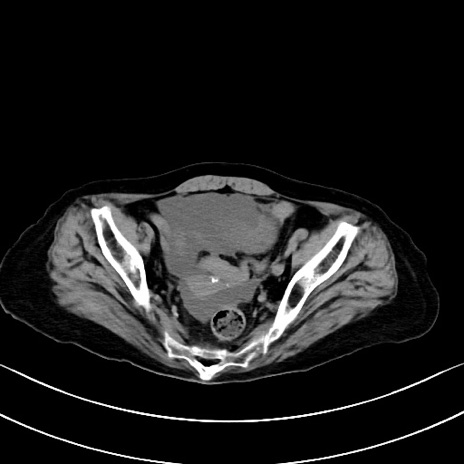

横断像

他院CT